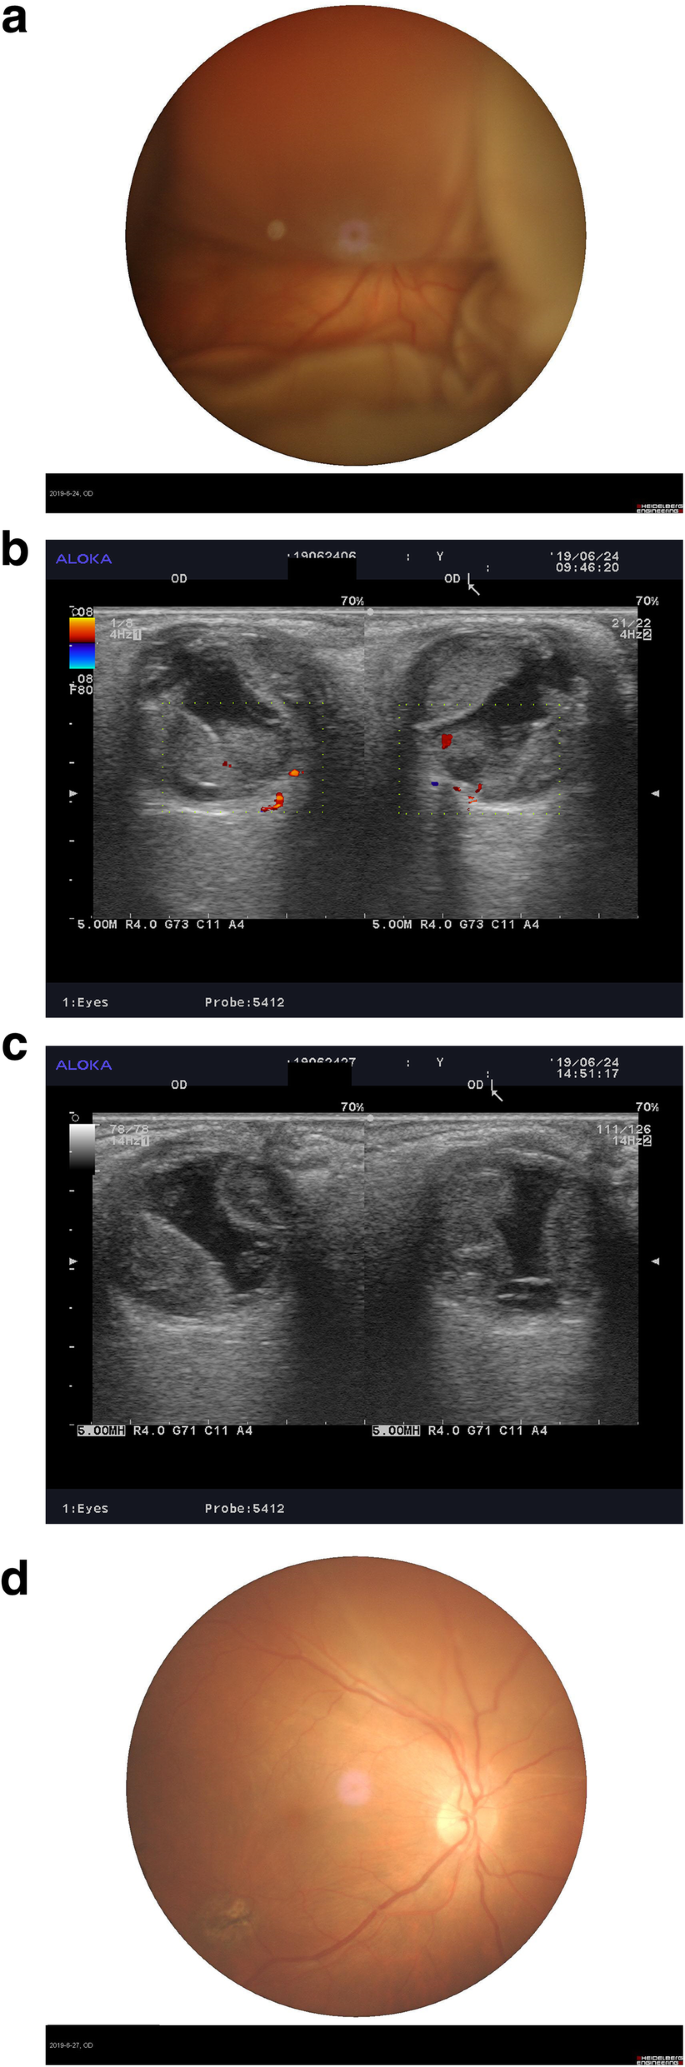

Case 2: patient was a 46-year-old male who had swelling with pain in the right eye for three hours after the second IOL ciliary sulcus implantation in a vitrectomized eye. The patient had previously received PPV and foreign body removal from the right eye two months before. The vision was LP and the intraocular pressure was 41 mmHg, with diffuse SCH involving the posterior pole with local retinal detachment but no retinal hole. The kissing sign could be seen on ultrasound examination. As no significant change occurred after four days, the patient was given a rt-PA injection in the suprachoroidal space and single suprachoroidal drainage was performed. Three days after drainage, the patient’s vision was 20/60 with an intraocular pressure of 8 mmHg, and a bulge was only seen in the upper choroid. Reexamination was carried out two months after surgery at which time the patient’s vision was 20/30 and both the fundus retina and choroid were flat (Fig. 4).

Fundus image and ultrasound examination of Case 2. a is a fundus image of the fourth day of DSCH; b is an ultrasound examination of the fourth day before rt-PA injection; c is an ultrasound examination showed partial liquidation of SCH 4 h after rt-PA injection; d is a fundus image of the third day after choroidal drainage showing that a bulge can only be seen in the upper choroid